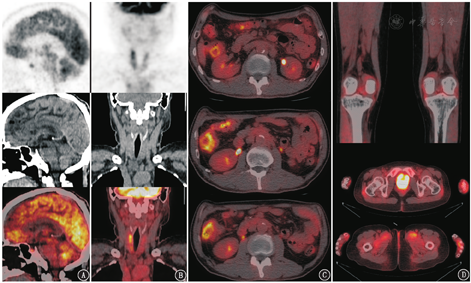

影像学上免疫相关肺炎主要表现为不同类型的间质性肺疾病,大致可分为机化性肺炎、非特异性间质性肺炎、过敏性肺炎、弥漫性肺泡损伤几大类[10]。但免疫相关肺炎需要与肺部感染鉴别,二者在肿瘤患者治疗期间都比较容易出现,影像表现有相似,而治疗方向却相反(糖皮质激素与抗生素等)。如图4是1例纵隔大B细胞淋巴瘤患者,曾接受化疗、自体干细胞移植、嵌合抗原受体T细胞回输、抗PD-1治疗,患者抗PD-1治疗8个月后出现了胸闷、气短、血氧饱和度下降,18F-FDG PET/CT示双肺多发磨玻璃、斑片及实变影,以中上肺、中央带分布为著,实变者内见支气管充气影,病灶代谢不同程度增高,SUVmax为9.7,最终临床诊断肺孢子菌肺炎,混合巨细胞病毒感染,予复方磺胺甲恶唑、更昔洛韦、泼尼松治疗后,患者症状缓解、肺部阴影消失。

18F-FDG PET/CT上常见到的irAEs还有免疫相关性垂体炎(图5A)、甲状腺炎(图5B)、结肠炎(图5C)、关节炎(图5D)等。需要注意的是irAEs容易出现在治疗后2~3个月,但有时也可以延迟至近2年后出现,且停止治疗后仍可进展[11]。